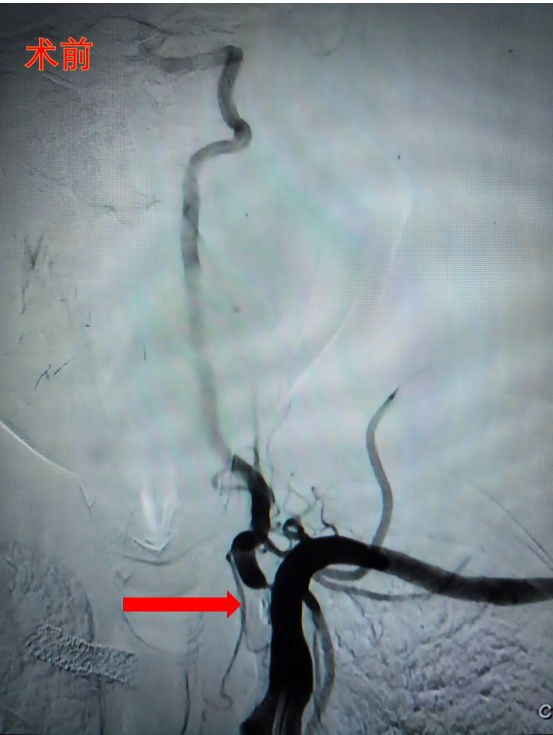

椎动脉作为大脑后循环供血的主要通路,其开口部位因血流冲击及解剖特点,容易形成动脉粥样硬化性狭窄。患者常表现为反复头晕、行走不稳,严重时可能引发后循环脑梗死,导致残疾甚至危及生命。面对这一临床难题,传统的支架植入术虽能短期内恢复血流通畅,但存在支架内再狭窄、长期服用双抗药物等局限。

精准定位:在数字减影血管造影(DSA)系统引导下,将特制的药物涂层球囊精准输送至椎动脉狭窄段;

靶向治疗:球囊在病变部位扩张时,不仅可机械性扩张血管管腔,其表面的紫杉醇药物还可高效渗透至血管内膜,有效抑制血管壁的病理性增生;

无植入理念:手术完成后,球囊导管完全撤出体外,实现了“治疗即走”的理想效果,避免了传统支架作为异物长期存留体内的各种隐患。